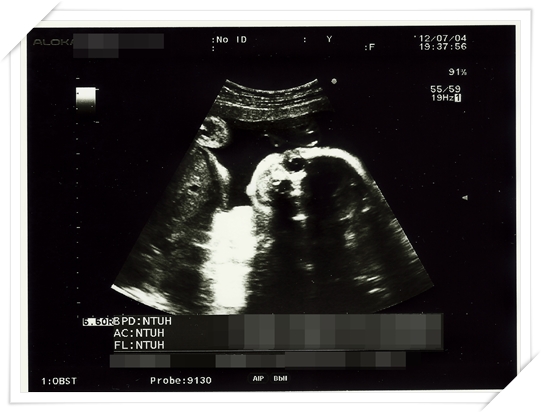

好期待可以看看超音波 更期待可以拿到最新的照片

而且事實證明 小鴨也真的長得比較快

都拜高蛋白所賜啦~~~~

他的“三圍” 可是越來越 “傲人” 了呢 哈哈哈哈哈!!

(這裡的三圍指的是 頭圍 大腿骨長度 以及身長 別想歪阿~~~)